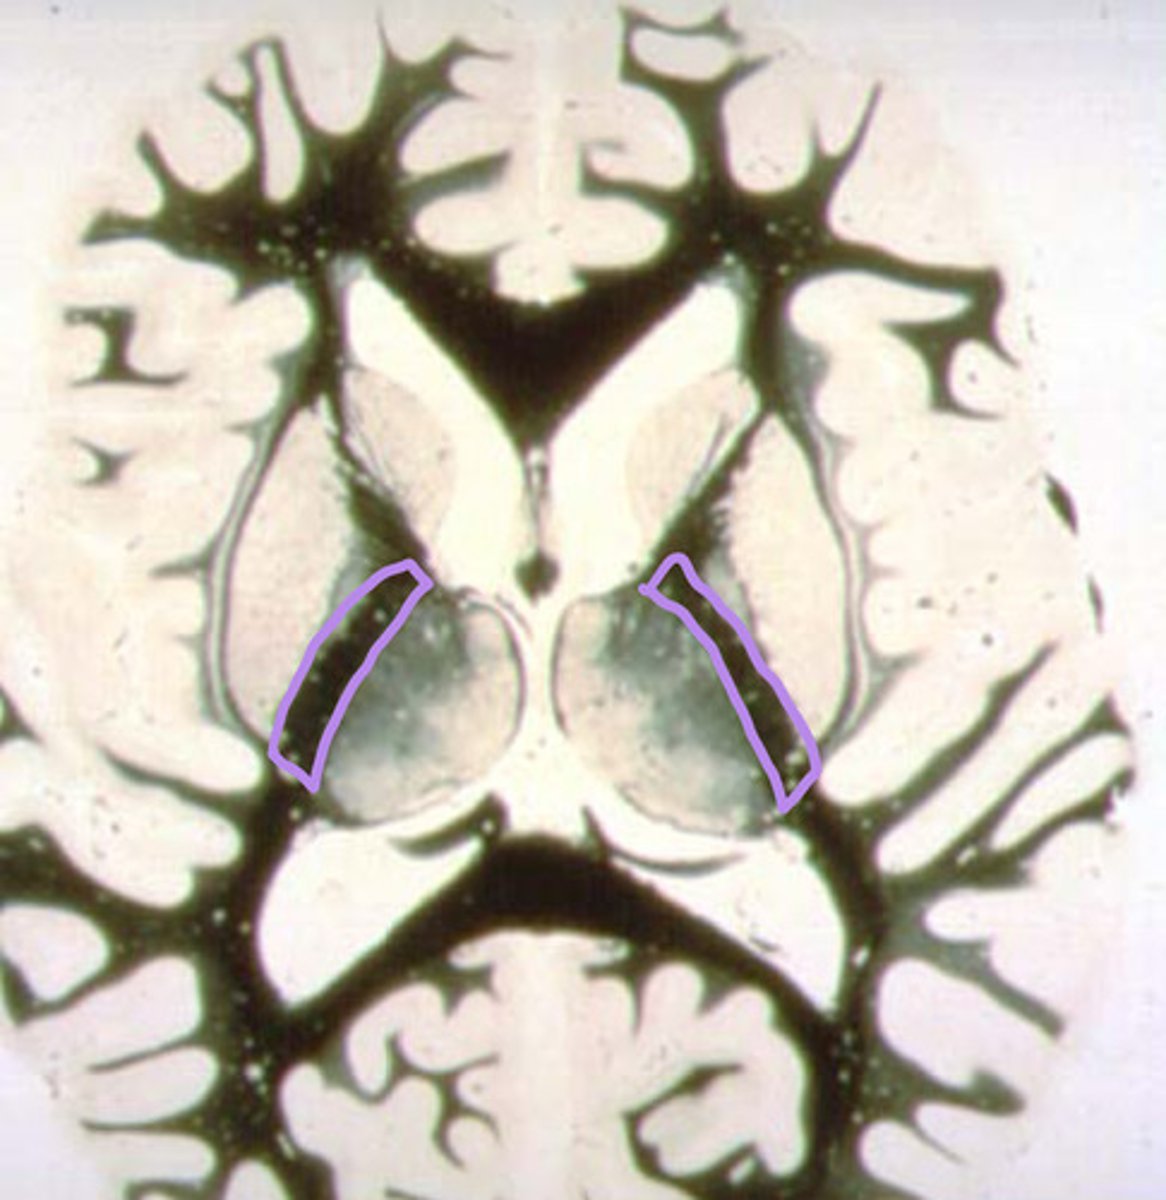

posterior limb of the internal capsule

Which structure contains all 3 body pathways: voluntary motor pathway, posterior column/medial lemnicus, anterolateral system?

identify the structure